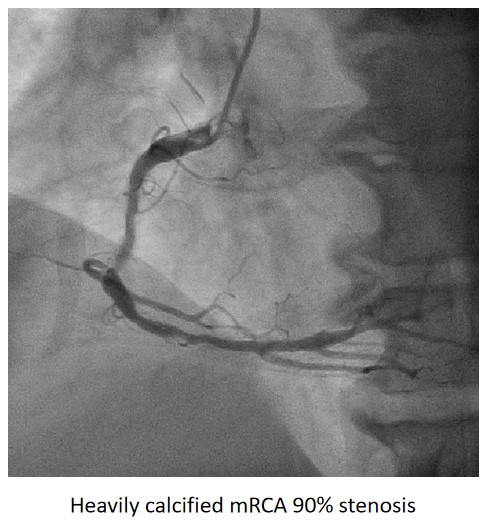

Urgent coronary angiography showed smooth LMCA with severe 3-vessel involvement. There was diffuse LAD lesion with critical stenosis at proximal-to-mid segment. Mid-segment of LCx was 90% stenosed while RCA was heavily calcified with critical stenosis at its mid segment. Our strategy will be complete revascularisation by employing DCB-only strategy.

Complete revascularisation was achieved with 2-staged procedures. Up-front plaque modification with rotational atherectomy/IVL with IVUS was planned but limited by patient¡¯s cost constraint. Vascular access obtained with transradial puncture with 6 Fr sheath. Guiding catheter (GC) Judkins Right 4.0 (Cordis, USA) 6 Fr was used to engage right coronary ostium. Runthrough Floppy (Terumo, Japan) wire was wired down RCA. Pre-dilatation balloons were unable to cross the heavily calcified mRCA lesion. Next, GC was changed to Amplatz Left 1.0 (Cordis, USA) for better support and proceeded for further lesion preparation with cutting balloon Wolverine (Boston Scientific, USA) 3.5 x 10 mm and DCB Prevail (Medtronic, USA) 3.0 x 20 mm was deployed. We scheduled him for staged PCI to the left coronaries in 2 weeks time via transradial approach with 6 Fr sheath. GC XB LAD 3.5 (Cordis, USA) 6 Fr was used to engage left coronary ostium. Runthrough Floppy was wired down LCx. Mid-distal LCx was prepared with Pantera Pro (Biotronik, Germany) 2.5 x 15 mm and DCB Pantera Lux (Biotronik ,Germany) 3.0 x 15 mm was deployed. Finally, we wired down LAD with Runthrough Floppy. Mid-distal LAD lesion was prepared with Pantera Pro 2.5 x 15 mm and DCB Pantera Lux 3.0 x 30 mm was deployed. Proximal LAD lesion, which was calcified, was further prepared with Wolverine 2.5 x 10 mm before DCB Pantera Lux 3.5 x 30 mm was deployed. Final post-PCI results were acceptable, achieving complete revascularisation for him.